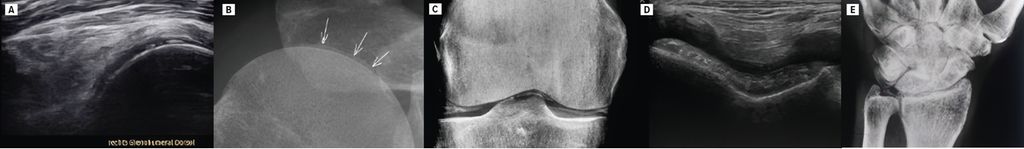

En cas de syndrome polymyalgique, il faut toujours envisager une CPPD. La prévalence de la CPPD (5%) est ainsi encore plus élevée que celle de la PMR (1%).4 Également appelée pseudogoutte, elle se caractérise par des dépôts de cristaux de pyrophosphate de calcium dihydraté sur le cartilage, les articulations, les ligaments, les tendons et les bourses. Ces dépôts peuvent être observés sous forme de calcifications à la radiographie conventionnelle et à l’échographie des articulations (Fig.1). Ce résultat radiologique, qui peut être détecté chez 15% des personnes âgées de >60 ans asymptomatiques, est appelé chondrocalcinose. On trouve typiquement des dépôts sur les articulations de l’épaule (sur le cartilage hyalin de la tête humérale et sur le fibrocartilage du labrum glénoïdal ainsi que du disque articulaire de l’articulation acromio-claviculaire), de la hanche (sur le fibrocartilage du labrum acétabulaire), du genou (sur le cartilage hyalin du fémur et du tibia, sur le fibrocartilage des ménisques) ainsi que du poignet sur le «triangular fibrocartilage complex» (TFCC). Une arthrose scapho-trapézo-trapézoïdienne (STT) dominante avec une rizarthrose comparativement faible, des ostéophytes au niveau des articulations métacarpophalangiennes (MCP) II et III sont également des signes typiques à la radiographie ainsi qu’à l’échographie. La colonne cervicale peut également être touchée dans des cas plus rares, avec des calcifications au niveau du ligament transverse de l’atlas autour de la dent de l’axis, ce qui peut conduire à un «crowned dens syndrome» accompagné de douleurs cervicales aiguës. Dans 20% des cas, la radiographie ne révèle aucune calcification au sens d’une chondrocalcinose. La recherche de cristaux de pyrophosphate de calcium dans le liquide synovial est plus sensible, de sorte qu’une ponction articulaire à visée diagnostique doit être effectuée chaque fois que possible en cas d’épanchement articulaire.

Fig.1: Radiographies et échographies de patients présentant une CPPD en tant que diagnostic différentiel principal de la polymyalgie rhumatismale. Calcifications au niveau du cartilage hyalin de la tête humérale à l’échographie (A) et à la radiographie (B); calcifications au niveau du cartilage hyalin du fémur ainsi que du fibrocartilage du ménisque à la radiographie (C) et du cartilage hyalin du fémur à l’échographie (D); calcifications au niveau du TFCC à la radiographie (E)